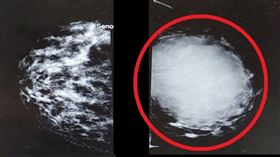

輕忽乳頭分泌物 45歲女養出7x6公分腫瘤

45歲的黃女士約一年前開始出現左乳頭斷斷續續出血的情...